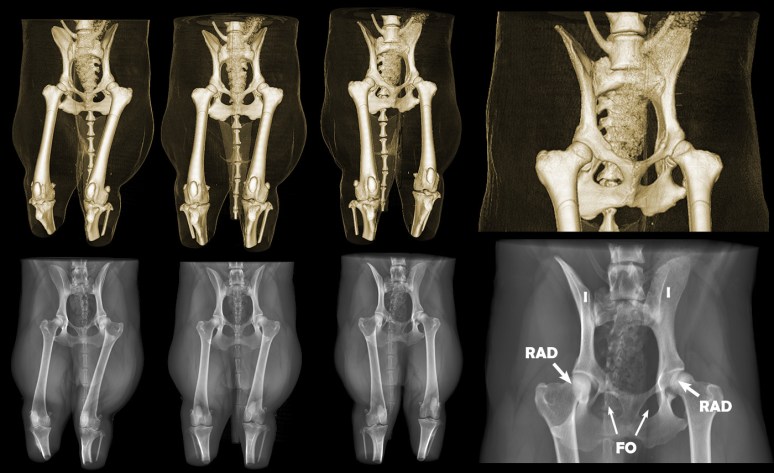

Ces effets inhérents à la radiographies sont influencés par la position du patient examiné et du détecteur (plaque) et influencent l’apparition des structures radiographiées. Or, ce concept est difficile à comprendre pour les novices. À partir de ce modèle, des images radiographiques peuvent être simulées dans tous les plans et avec différents effets de magnification ou de distorsion permettant aux étudiants de mieux saisir ces concepts. Par exemple, l’impact du positionnement radiographique du bassin d’un chien sur l’apparence des articulations coxofémorales peut être enseigné plus facilement. L’une des variables à considérer lors du diagnostic précoce de la dysplasie de la hanche chez le chien est le degré de recouvrement des têtes fémorales par le rebord acétabulaire dorsal (RAD). La figure ci-bas montre l’impact du positionnement du bassin sur le degré de recouvrement et sur l’apparence de chaque aile iliaque (I) et foramen obturateur (FO), laquelle nous guide dans l’évaluation du positionnement (ces structures anatomiques devant être bien symétriques pour permettre une évaluation correcte du degré de recouvrement fémoral, lequel doit atteindre au moins 50%).